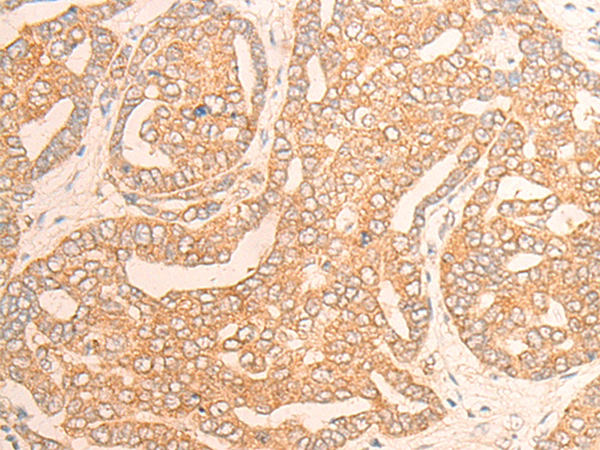

分类: 科研抗体货号: P13262别名: DMN; SYN应用: IHC反应种属: Human